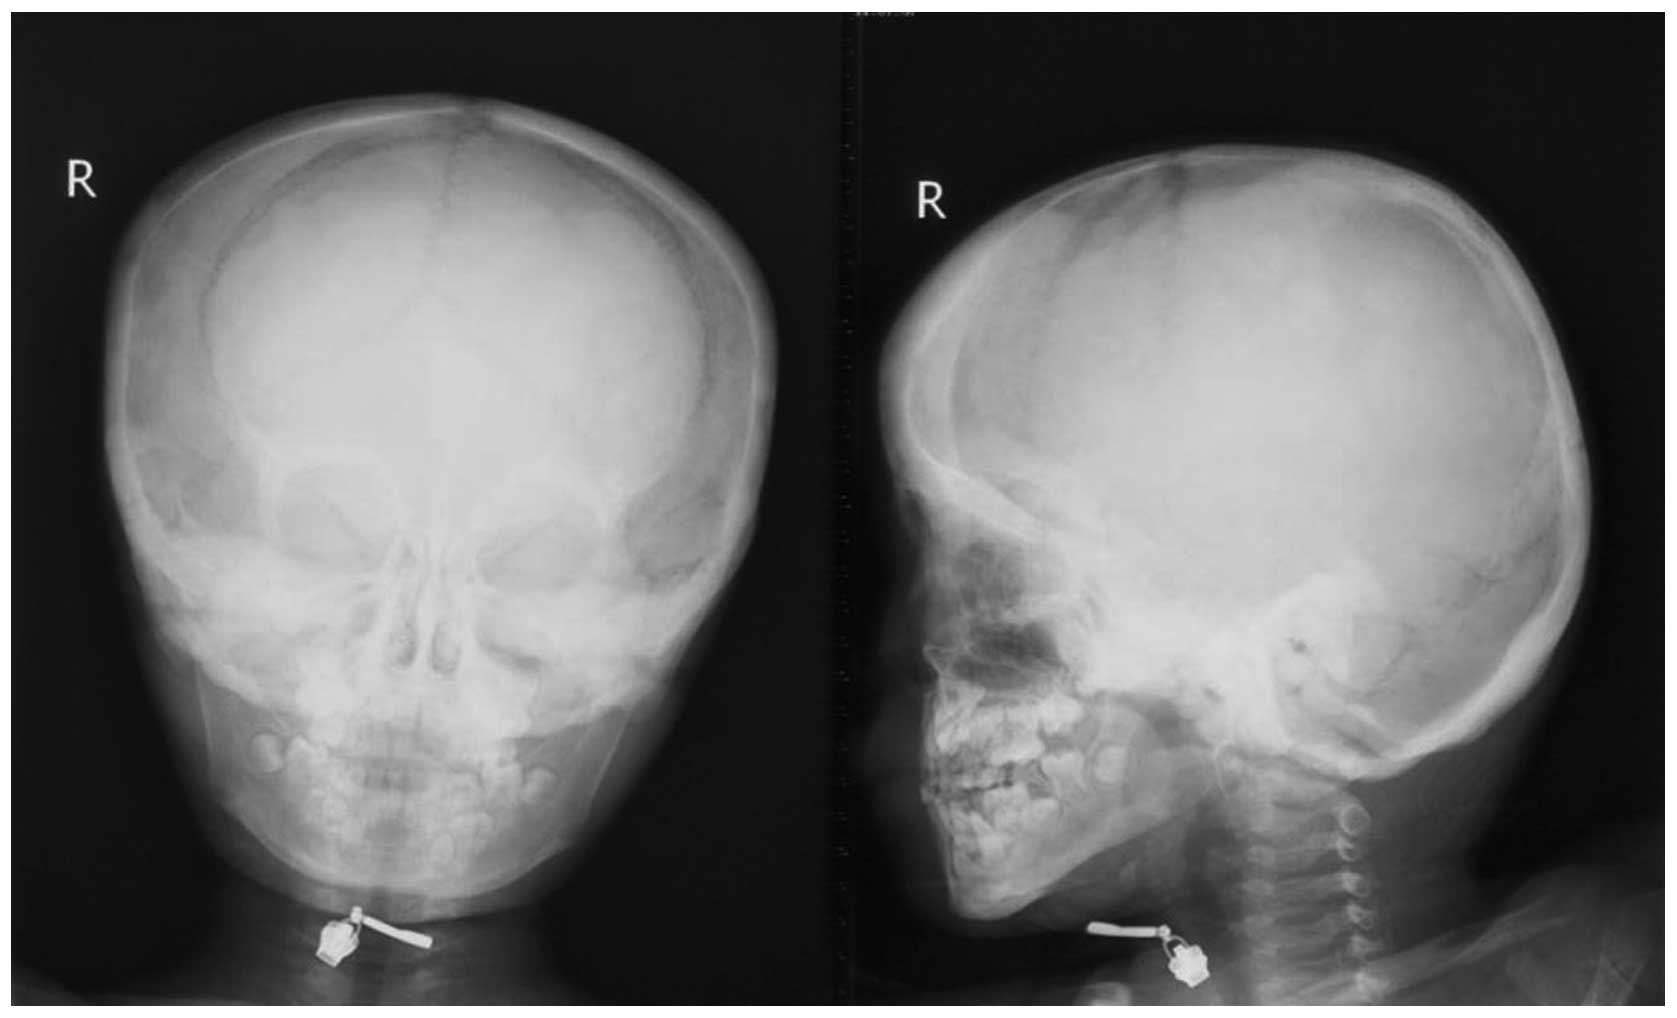

Анатомия детского черепа: Рентгеновские снимки и описание